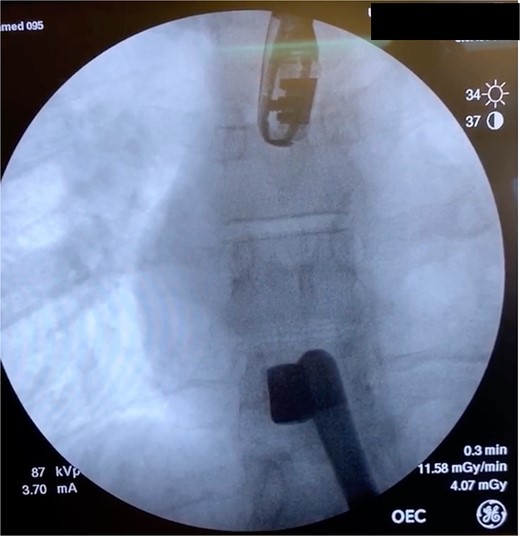

A 36-year-old male presented with multiple thoracoabdominal GSW (4 GSW in the left axilla, 2 GSW right flank). The patient had decreased breath sounds on the left. Initial vital signs were heart rate 141, blood pressure 70/40, respiratory rate 22, saturation 92% on 15 L non-rebreather, GCS 14. The patient underwent a left thoracostomy tube with 1000 mL initial output and a 9F left femoral central line was placed. The patient was initially resuscitated with 2 units PRBC, 2 units FFP with no improvement in vital signs. A plain film X-ray in the trauma bay revealed multiple thoracoabdominal bullets (Fig. 3). The patient went emergently to the OR for hemorrhage control.

Plain film X-ray obtained in the trauma bay demonstrating multiple bullets overlying the cardiac silhouette and right abdomen.

Case 2 involved a hemodynamically unstable patient with multiple thoracoabdominal GSWs. The surgical team identified six GSWs and five retained bullets. The patient’s instability precluded CT imaging. A cardiac injury was suspected due to a bullet overlying the cardiac silhouette and significant chest tube output. Thoracotomy confirmed a cardiac injury with tamponade, necessitating immediate repair. The bullet trajectory suggested it passed through the heart and diaphragm into the abdomen. TEE revealed no intracardiac shunting, valve insufficiency, or bullet. The bullet injured the left ventricle and embolized to the aortic root, becoming symptomatic on hospital Day 7. A CT scan suggested an intravascular bullet near the aortic valve, confirmed by TEE showing severe aortic insufficiency. The patient required four operations for definitive management. This case underscores the risks of conservative management and the need for thorough evaluation in unstable patients.